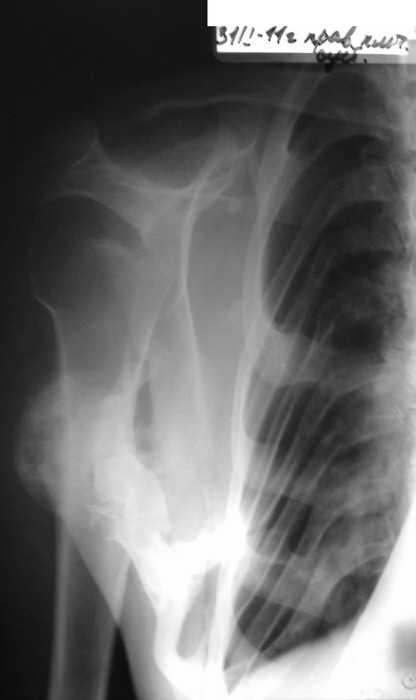

Врожденная аномалия, множественные экзостозы

Место болезни: при осмотре определяется - вынужденное положение верхних конечностей в плечевых и локтевых суставах, множественные опухолеподобные образования вдоль позвоночника и по наружной поверхности верхней трети левой бедренной кости округлой формы, с четкими контурами, неподвижные, безболезненные, каменистой плотности. приводяще-отводящая контрактура в обеих плечевых суставах, сгибательно-разгибательная контрактура в обеих локтевых суставах с сохранение про- и супинационных движений. Объем движений в пальцах кисти и лучезапястных суставах в полном объеме без ограничений, безболезненный.

Диагноз: врожденная аномалия развития шейного отдела позвоночника с резким нарушением функции в плечевых и локтевых суставах, множественных костно-хрящевые экзостозы, оссифицирующий миозит.

рентгенограммы

это fibrodysplasia ossificans progressiva, генетически обусловленная прогрессирующая метаплазия соединительной и мышечной ткани в костную. Лечится (вернее, тормозится) консервативно, после попыток оперативного лечения и после травм - прогрессирует.